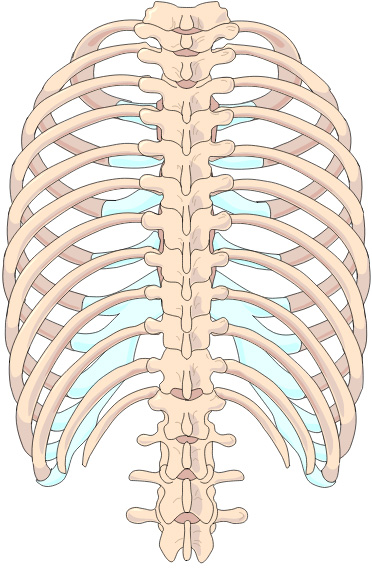

Der Körper besteht aus drei Hauptteilen:

Becken als Mittelebene, Oberkörper wird auf die Mittelebene abgestützt, die Beine mit den Füssen werden am Becken aufgehängt.

Ist die Mittelebene nicht waagrecht und senkrecht in der Mitte ausgerichtet, kann weder der Oberkörper noch die Beine ausgeglichen abgestützt oder aufgehängt werden.

Skelett

Das Skelett besteht aus einzelnen Knochen, Gelenken, Wirbelkörpern und wird über Bänder, Sehnen und Muskeln zusammengehalten und bewegt. (ca. 206 Knochen im erwachsenen Alter)

Zusammengefasst besteht das Skelett aus drei Teilen, der Mittelebene dem Becken, abgestützt darauf der Oberkörper und am Becken angehängt die Beine mit den Füssen. Über eine schiefe Beckenebene verändert sich automatisch die Oberkörperhaltung. Diese Fehlkräfte wirken wiederum auf das Becken und dadurch auch auf die Bein- und Fussstellungen, die diese Fehlbelastungen auf den Boden übertragen.